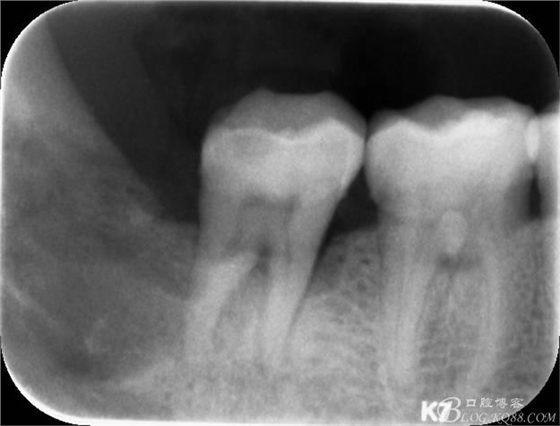

48未萌出,47遠(yuǎn)中可探及深約7mm的牙周袋。頰側(cè)47、48之間牙齦紅腫,有少量血性滲出。X線根尖片顯示:48牙冠反轉(zhuǎn)倒置,47遠(yuǎn)中牙槽骨吸收明顯。CBCT顯示:48牙冠近中面位于下頜管內(nèi)。

10.術(shù)后根尖片: